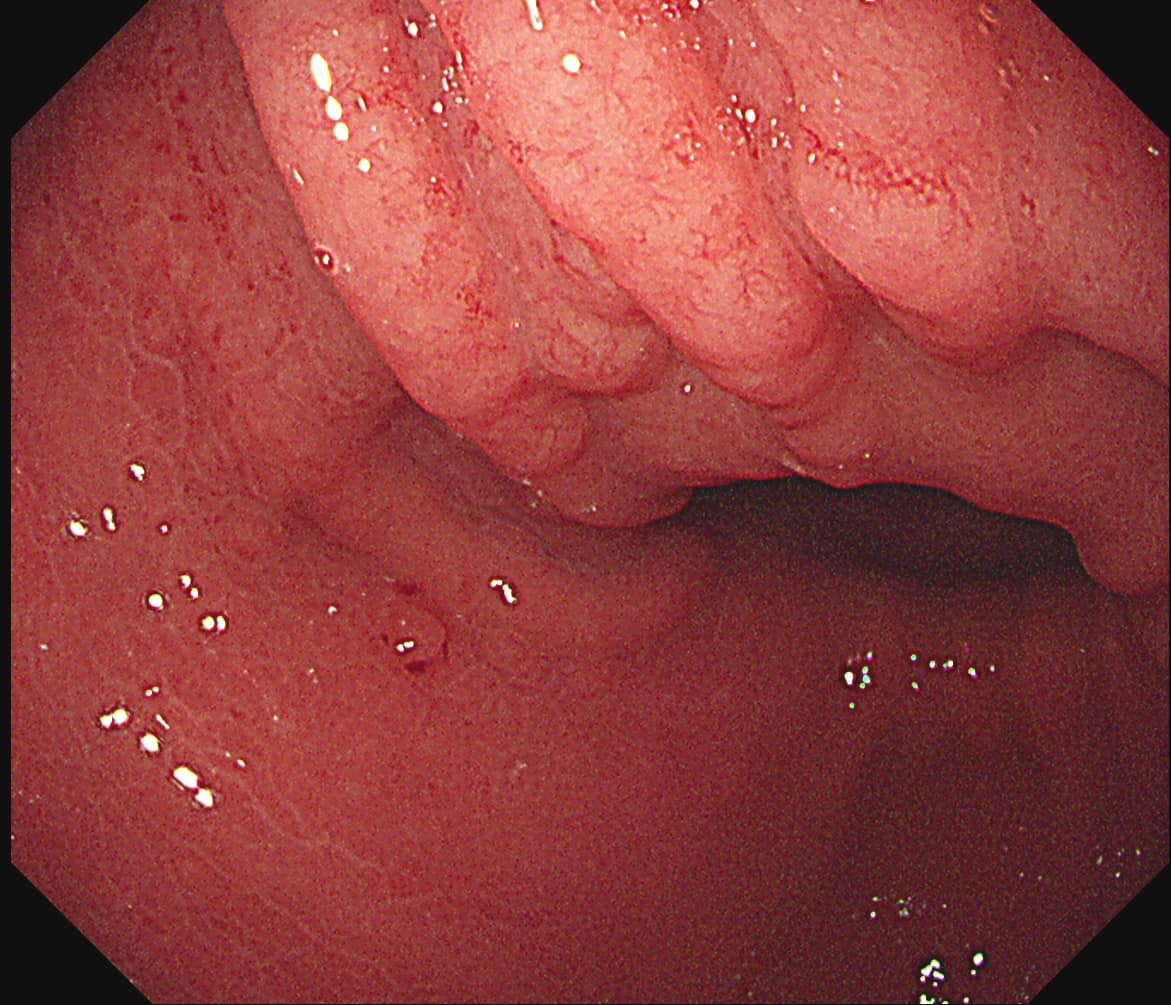

台北禾馨民權健康管理診所院長林相宏3月8日在臉書粉專《胰臟醫師 林相宏》分享「健檢的價值」,他提到曾有一名30歲女士來診所做身體檢查,照胃鏡時,雖未見腫瘤,但他眼尖發現病患的胃壁有許多小結節突起,他表示,「我喜歡形容成像『苦瓜表面』,或像『健康步道』」。

林相宏提高警覺,在仔細追問得知,患者沒有胃悶、胃痛、食慾體重下降、解黑便、火燒心等胃感染相關病症,只有偶爾脹氣、打嗝。林相宏認為事有蹊蹺,應該先做更深入的檢查,所以進一步安排強化內視鏡檢查,才發現患者的胃表面黏膜已出現不規則、類似龜裂的樣子,經切片診斷結果證實罹患低惡性度的淋巴瘤,亦「胃淋巴癌(MALToma)」。